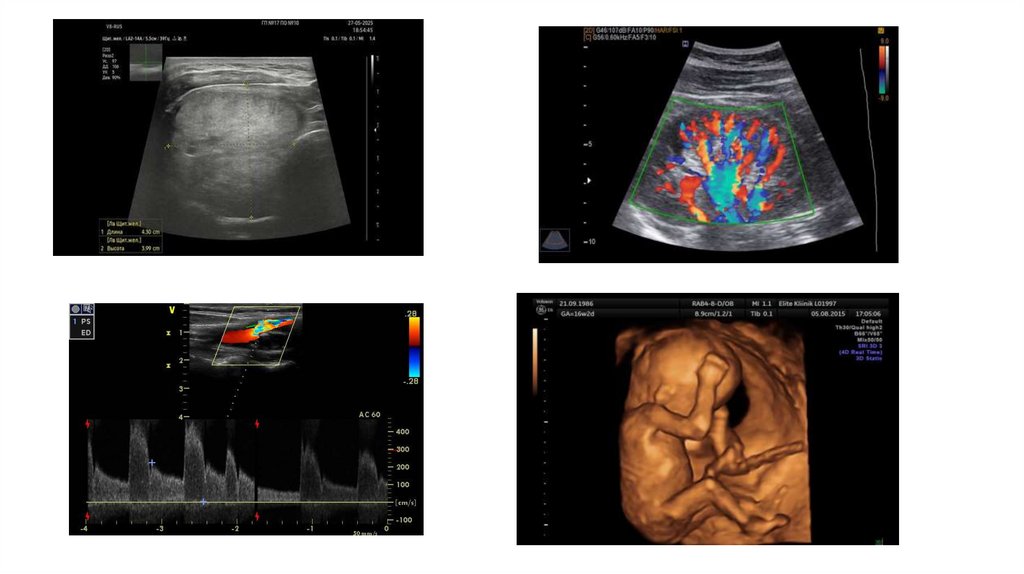

Методы ультразвуковой диагностики:

Эхография;

Допплерография

Триплексное исследование;

Трехмерное исследование (объемная визуализация);

Эластография;

Ультразвуковое исследование с применением контрастирующих

препаратов;

• Мультимодальная визуализация.